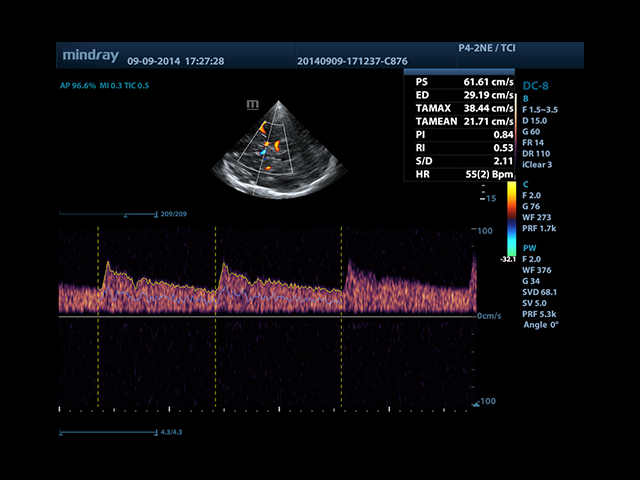

• Автоматическая трассировка допплеровского спектра с расчетом параметров и индексов

• Smart Doppler™ - автоматическая подстройка расположения рамки цветового допплера и контрольного объема импульсно-волнового допплера

• TDI (Tissue Doppler imaging, including TDI Color, Power, PW and M mode) - пакет тканевой допплерографии, включая цветное картирование, импульсный тканевой допплер, энергетический тканевой допплер и тканевой М-режим

• TDI Quantification Analysis Software - количественный анализ тканевого допплера (необходима опция TDI)